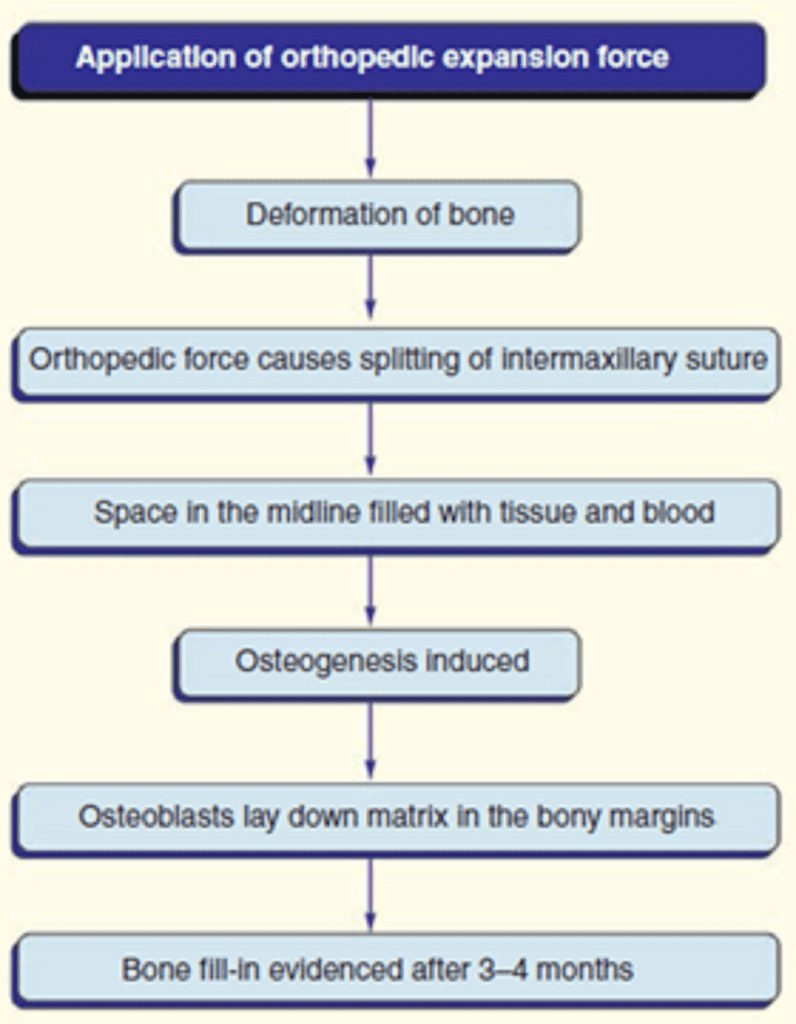

III.Principle of RME

The basic principle of the appliance involves the generation of forces that are capable of splitting the mid-palatine suture for expansion but some dentoalveolar expansion effects are also produced. Hence, the forces should be definitely more than the usually used orthodontic forces. The forces generated are close to 10 to 20 pounds.

An expansion of 0.2 to 0.5mm should be achieved per day. The screw when turned 90 degrees, the mid-palatal suture will open by 0.2 mm and narrows the periodontal membrane by 0.1 mm on each side. The screw is activated at between 0.5 to 1mm per day and about 1 cm of expansion can be expected in 2 to 3 weeks. The activation schedules tend to vary depending upon the age of the patient and form of the appliance. According to Proffit, most screws open 1mm per complete revolution, so that a single quarter turn produces 0.25mm of tooth movement.

The suture expansion is around 20 to 50% of the total screw expansion (Bazargani et al., 2013). RME also leads to an increased dimension of the nasal cavity (Ballanti et al., 2010) and moderate evidence exists that RME in growing children improves the conditions for nasal breathing from a short-term perspective (Baratieri et al., 2011).

- Mid-palatal suture does not open evenly but opens in a ‘V’ fashion.

- The broad end of V is in anterior region and apex of V is at the posterior region.

- Appearance of median diastema.